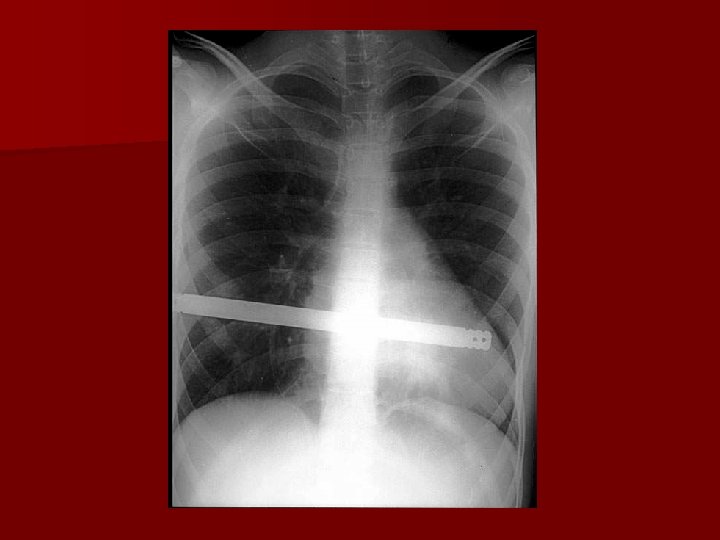

Diaphragmatic hernia

1 rok później